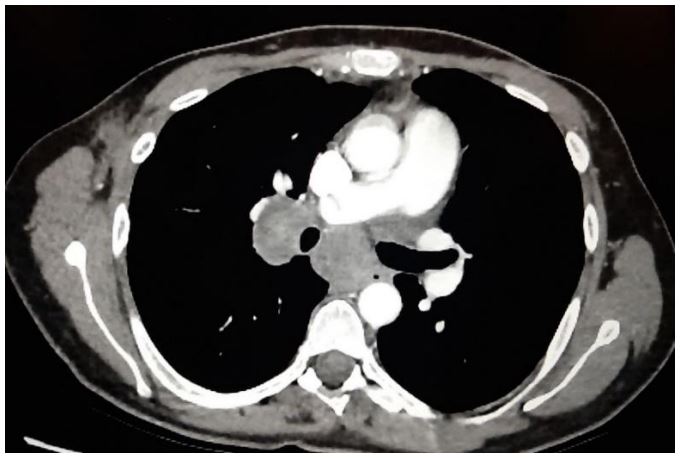

Initially, 4 cm right-sided breast mass was identified on ultrasound (Figure 1). From there, a core needle biopsy was performed, which demonstrated a fibroadenoma. However, the histology from the ensuing lumpectomy demonstrated the presence of a malignant PT. After several courses of radiotherapy, the discovery of the right-sided axillary lymph node necessitated PET-CT, which showed high intake of FDG (Figure 2). The corresponding core needle biopsy confirmed that it contained metastasized PT. After performing bilateral mastectomy with right axillary lymph node dissection, the histology proved that the breasts were clear, but that 1/16 lymph nodes contained PT. Significantly, the occurrence of an additional axillary mass a couple months later prompted an abdominal and chest CT. This demonstrated metastases in the axillary, mediastinal, and retroperitoneal lymph nodes, with liver metastasis (Figures 3 and 4). No further biopsies were performed, and follow-up abdominal and chest CT demonstrated that the metastases had increased in size (Figures 5 and 6).

Figure 3: Chest CT demonstrating pathologic axillary and mediastinal lymph nodes.

Figure 5: CT demonstrating enlargement of axillary and mediastinal lymph nodes.